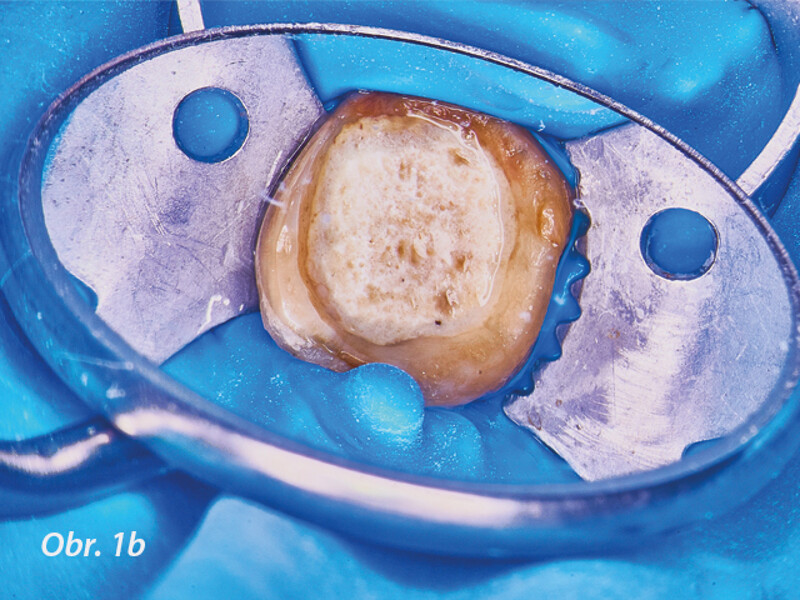

Řešení endodontických selhání